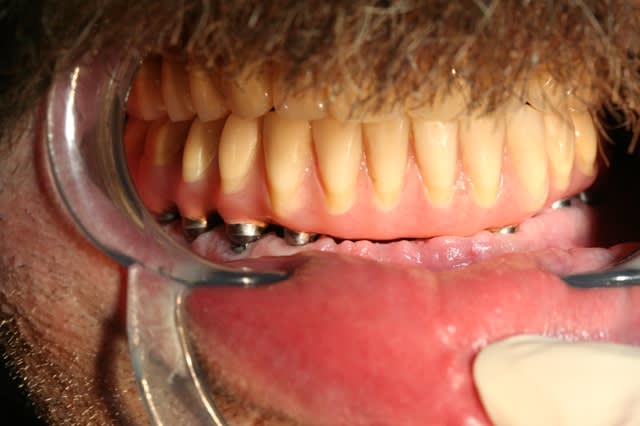

> j'avais promis de montrer la suite et la fin du cas.

>

> Alors voilà: empreinte pick-up mixte (silicone et plâtre snowhite), RIM avec

> cire calée sur des piliers hauts, et aujourd'hui retrait des implants

> provisoire et vissage de la prothèse.

il s'agit de dents et fausse gencive en résine.

l'extension se calcule, c'est 1.5 X la distance entre 2 droites parallèles (une qui passe par les bords postérieurs des implants les plus distaux et l'autre qui passe par le milieu de l'implant le plus antérieur)

ici je suis à X 1.6 , j'ai aussi,en quelque sorte, une "extension antérieure" du fait que les incisives sont vestibulées par rapport à l'implant médian et la patiente n'a pas non plus des masseters surpuissants.

cette solution est éprouvée et sur le prochain, je tacherai juste de donner une petite inclinaison distale aux implants distaux (comme l'avait suggéré noahaxeltiger)..1 mm de gagné c'est toujours interessant.